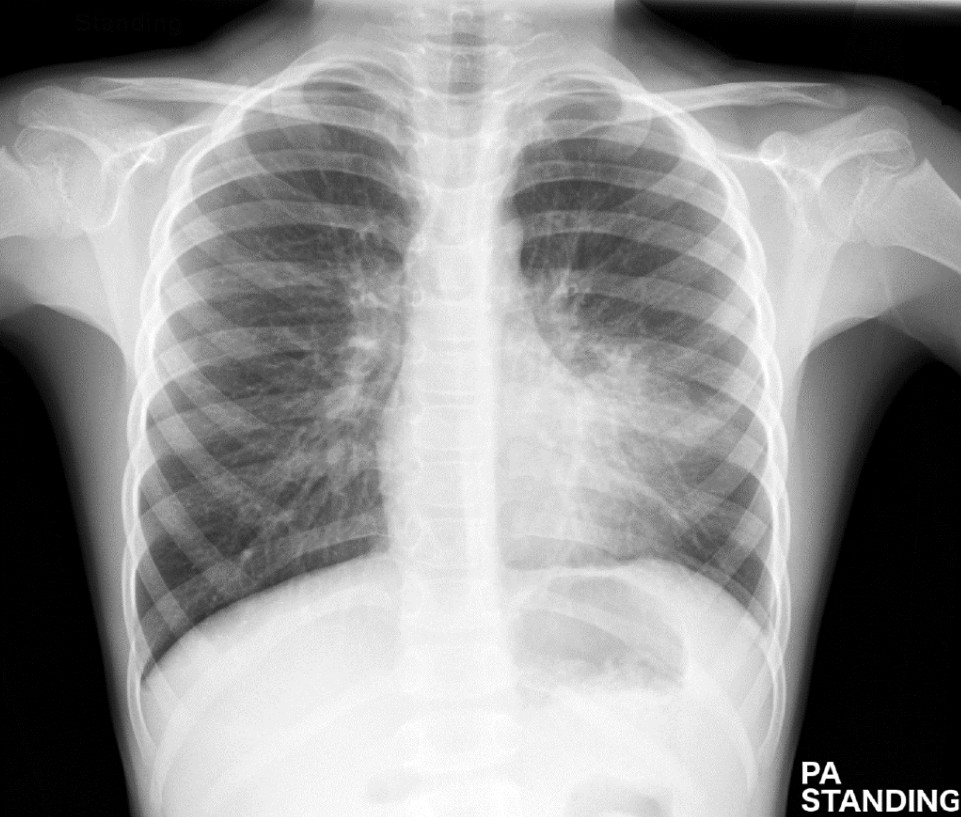

The mother brings the child to ED later in the shift. The child has become more unwell and looks flat but conversive. There is no stiff neck or photophobia. Urinalysis is unremarkable. T 39.5 RR 44 SpO2 88% RA --> 94% 4LNP HR 145 BP 95/50

3. Describe the most CXR significant finding and an overarching diagnosis. 2 marks

Question image